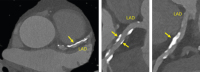

Abbildung 2: Coronary-CT scan showing heavy calcified plaques in the proximal LAD